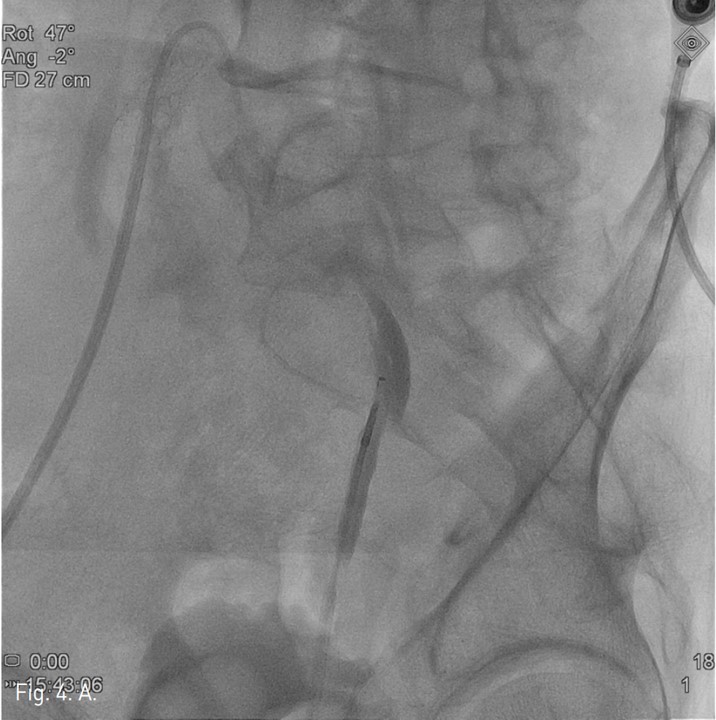

컴퓨터단층촬영 혈관조 영술과 고식적 혈관조영술에서 우측 총장골동맥에 석회화를 동반한 80%정도의 심한 협착이 있고, 좌측 총장골동맥에서 외장골동맥에 석회화를 동반한 완전 폐쇄의 소견이 있다 (Fig. 1A, IB). 우총대퇴동맥의 근위부에 10mm x 29mm Zenesis stent를 설치하였다 (Fig. 2). 0.035 inch guidewire로 좌측 총장골동맥의 기시부 폐쇄부위 통과를 시도하였으나 가성내강에서 진성내강으로 재진입이 되지 않았다 (Fig. 3). 좌측 외장골동맥 진성내강 내에 있는 ‘L-자’ 표시방향의 outback device가 보인다 (Fig. 4A), 좌측 외장골동맥 진성내강 내에 있는 'T-자’ 표시방향의 outback device가 보인다(Fig. 4B). Outback device를 이용하여 동맥내막을 천자후 0.014 inch guidewire를 가성내강 내로 진입시켰지만 좌측 총장골동맥-외장골동맥경 계부위에서 더 이상 진행되지 않았다 (Fig. 4C). 0.014 inch guidewire를 따라서 Davis catheter를 가성내강 내로 진입시키고 (Fig. 5A), 10mm snare를 삽입하여 Simmon catheter내부에 있던 microwire를 전진시켜 snare로 잡아 좌측 sheath로 뽑아내어 (Fig. 5B), 5Fr. Davis catheter를 대동맥 내부로 진입시켰다(Fig. 5C). 양측 총장골동맥 및 좌측 외장골동맥 스텐트 설치후 대동맥장골동맥조영술상에서 양측 장골동맥의 완전한 재개통을 보인다 (Fig. 6).

Fig. 4. A

Fig. 4. A. Radiograph taken while L-shaped marker of Outback device is seen.